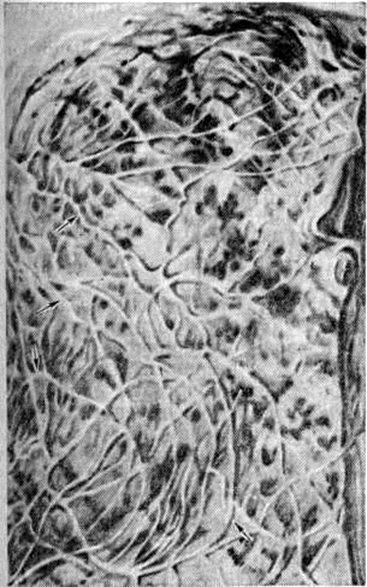

Рис. 2.

Макропрепарат плевры при раковом лимфангиите: лимфатические сосуды плевры утолщены (указано стрелками).